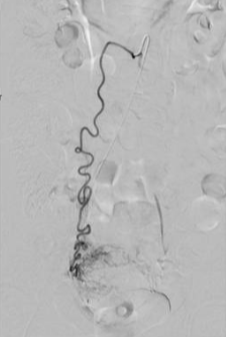

所有年龄超过 40 岁的患者, 卵巢受损 14%-43% 研究中闭经发生率(15%)与单纯UAE报告相似,可能与患者年龄(≥45岁)及卵巢储备自然下降有关。 ![]() 50岁,长期因子宫肌瘤导致月经出血过多,痛经和贫血。 子宫肌瘤栓塞术前,显示双侧子宫动脉发育不全,子宫肌瘤双侧卵巢动脉。 经皮股动脉穿刺双侧卵巢动脉栓塞,先500μm-700μm emboSphere 微球 术后4周,和6月的中短期随访,月经正常,子宫容积减少,贫血纠正,无卵巢功能衰竭。但看起来非灌注容积较少。 术后9月,由于子宫肌瘤持续存在,患者自己希望绝经,行全子宫和双侧卵巢切除术 术后病理,子宫内可见栓塞微粒伴有坏死,卵巢内也见栓塞微粒,但卵巢功能未受损。